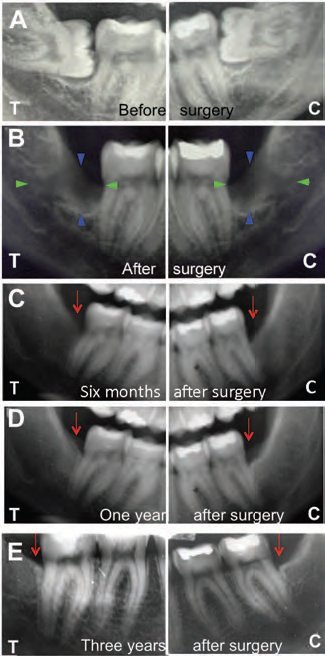

A study in the latest issue of STEM CELLS Translational Medicine shows how stem cells can be used to successfully repair the mandible after a molar extraction and that, years later, the new bone is still functioning properly. Interestingly, the regenerated bone is also hard, rather than the spongy kind normally found in the jaw.

The study is a follow-up to previous investigations by an international team of researchers in which they discovered that mesenchymal stem cells taken from dental pulp and seeded on a collagen scaffold successfully repaired the mandible bone. In this latest work, they checked on patients who had received the mandible bone grafts three years earlier to assess the stability and quality of the regenerated bone and vessel network.

They found the new bone had normal function and was richly vascularised, although it was much more compact than the spongy type normally found in the mandible. The team theorised that, most probably, regeneration of compact bone occurs because grafted dental-pulp stem cells do not follow the local signals of the surrounding spongy bone.